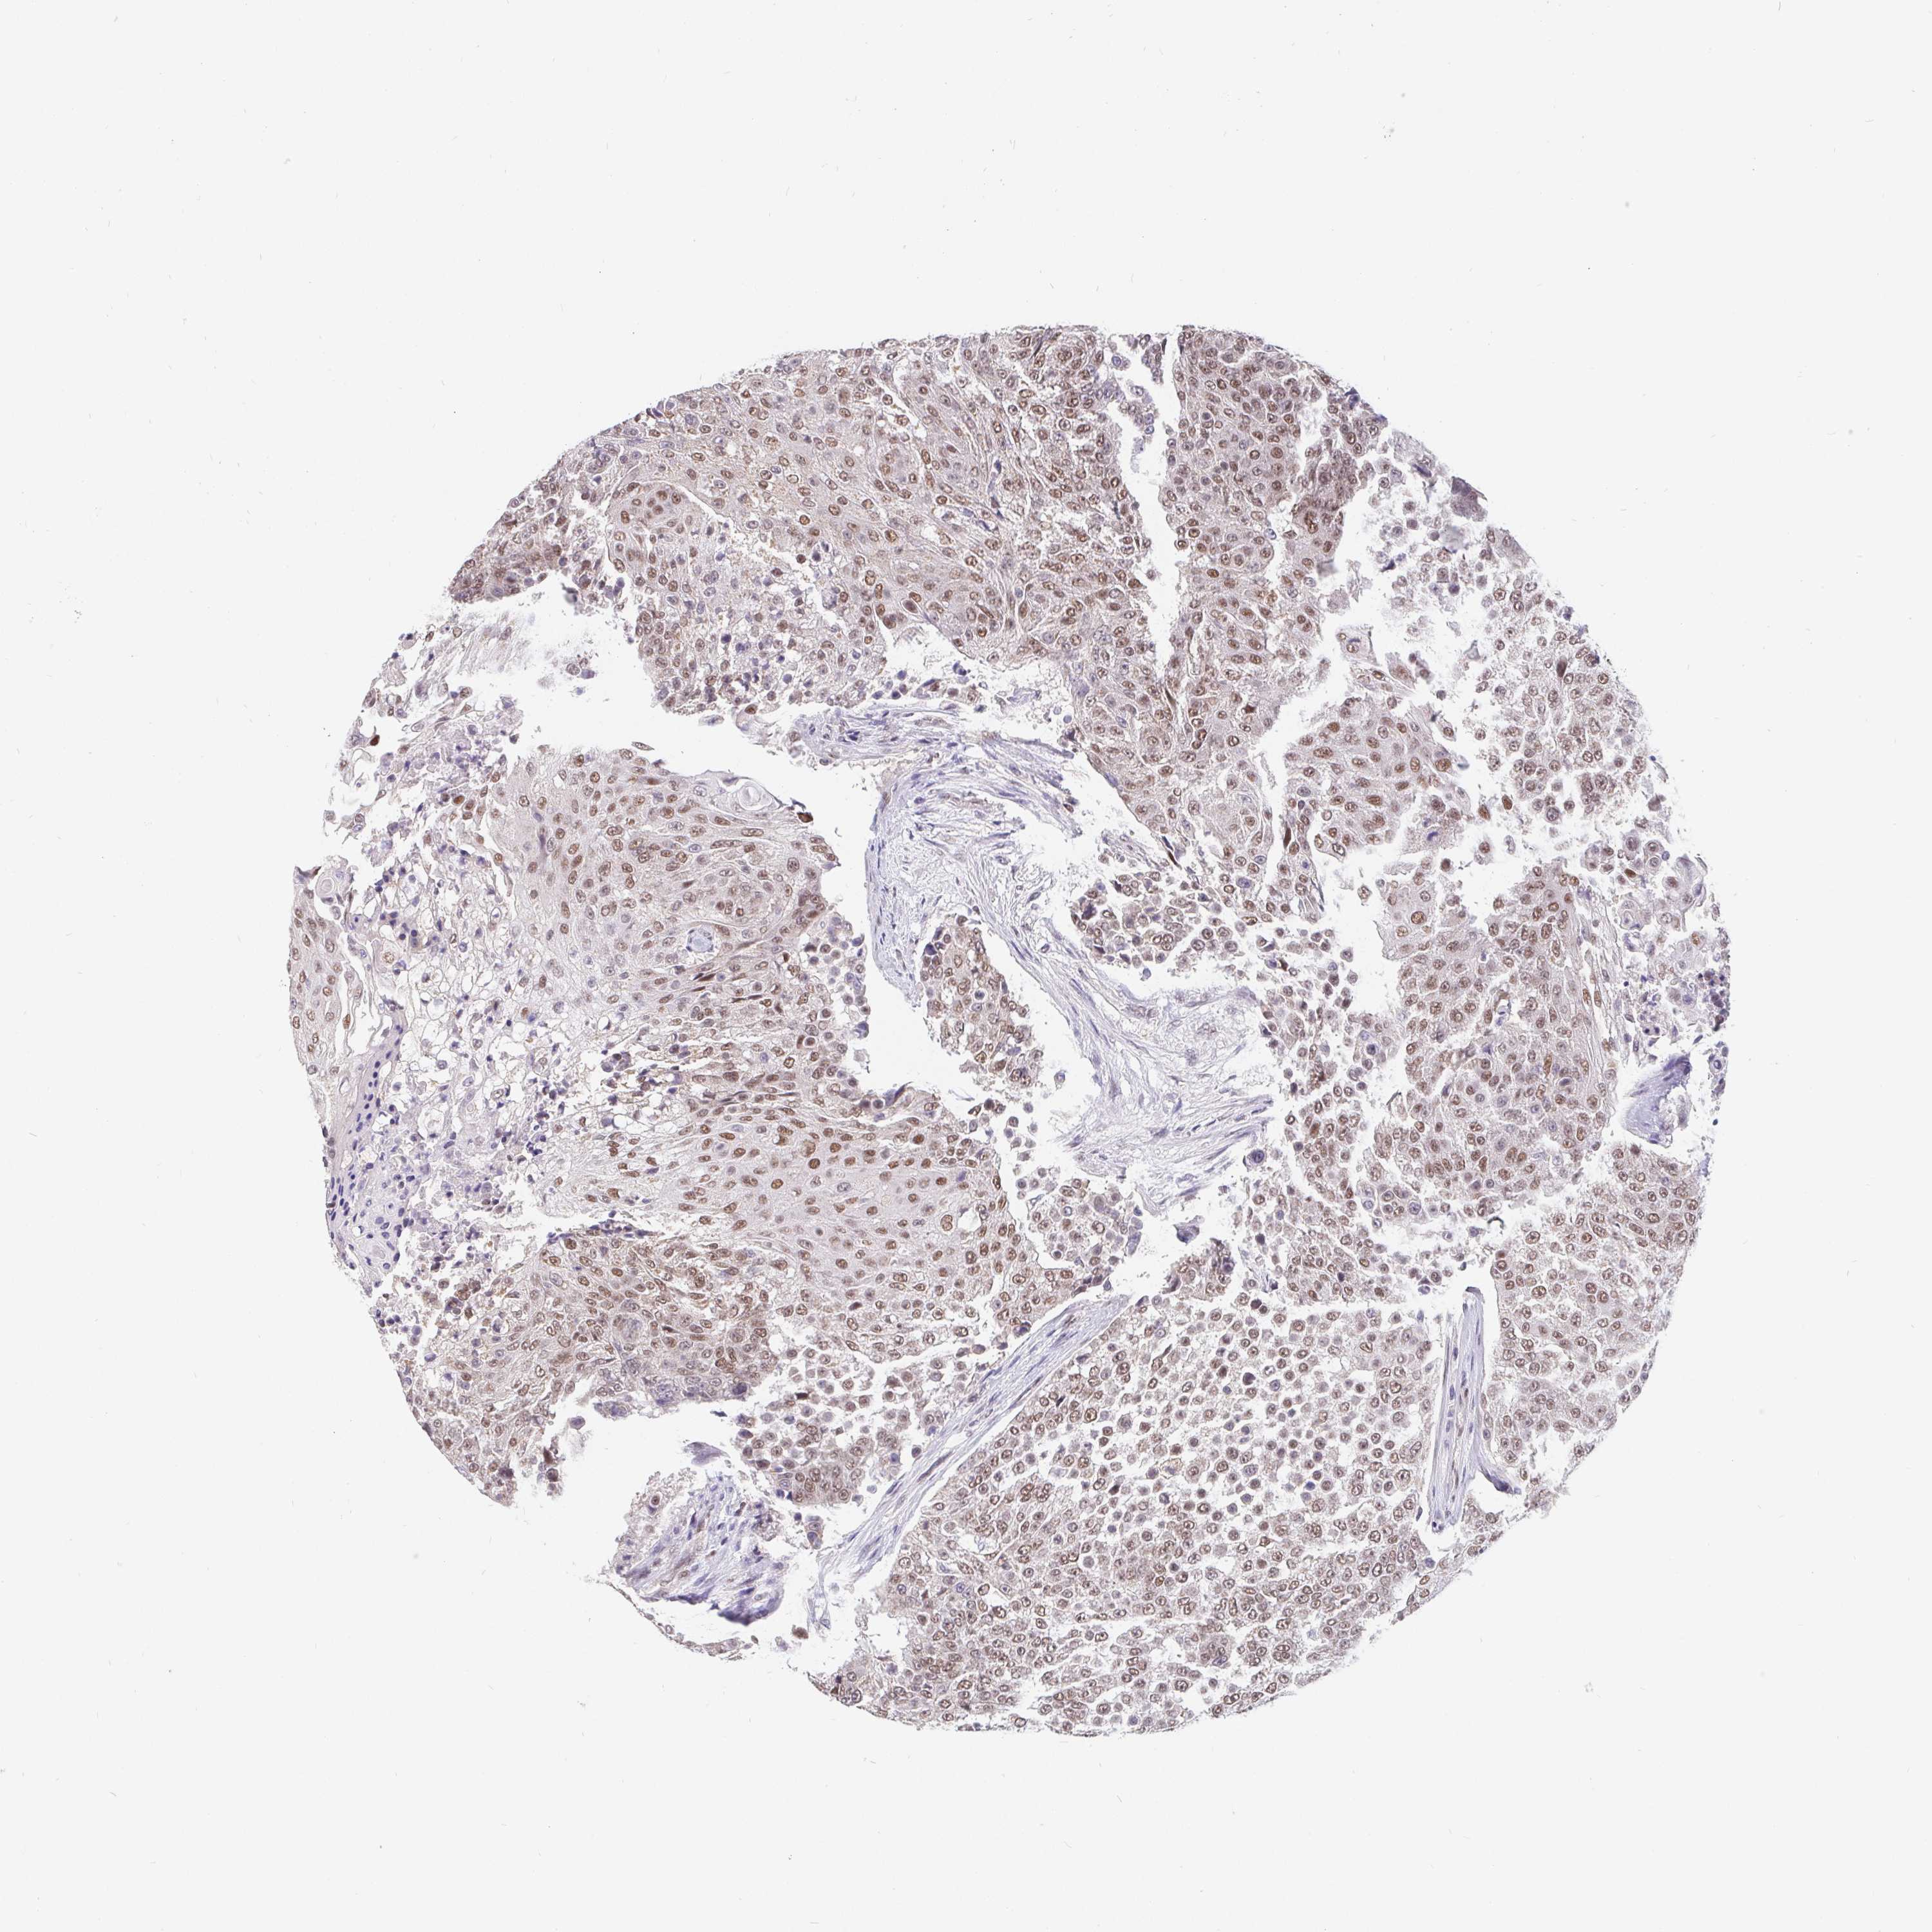

UROTHELIAL CANCER - Protein expressioni

A mouse-over function shows sample information and annotation data. Click on an image to view it in a full screen mode. Samples can be filtered based on level of antibody staining by selecting one or several of the following categories: high, medium, low and not detected. The assay and annotation is described here.

Note that samples used for immunohistochemistry by the Human Protein Atlas do not correspond to samples in the TCGA dataset.

Antibody stainingi

Antibody staining in the annotated cell types in the current human tissue is reported as not detected, low, medium, or high, based on conventional immunohistochemistry profiling in selected tissues. This score is based on the combination of the staining intensity and fraction of stained cells.

Each image is clickable and will lead to virtual microscopy that enables deeper exploration of all samples and also displays staining intensity scores, fraction scores and subcellular localization as well as patient and tissue information for each sample.

Antibody HPA064323

Antibody CAB002608

Staining

High

Medium

Low

Not detected

Intensity

Strong

Moderate

Weak

Negative

Quantity

>75%

75%-25%

<25%

None

Location

Nuclear

Cytoplasmic/membranous

Cytoplasmic/membranous,nuclear

Urothelial carcinoma, High grade

Urothelial carcinoma, NOS

Urothelial carcinoma, Low grade

Adenocarcinoma, NOS